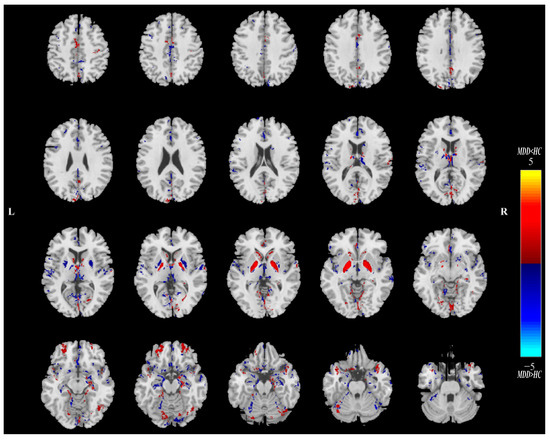

Figure 3.

The spatial maps of QSM_IC03 visualized at |Z| > 2, where the red brain regions (Z > 0) indicate higher QSM values in HC subjects than MDD participants, and the blue brain regions (Z < 0) indicate higher QSM values in MDD subjects than HC participants. MDD = major depressive disorder; HC = healthy control.

Twenty ICs for QSM and sMRI were estimated in this study. Intergroup statistics were applied using the two-sample t-test to analyze the mixing coefficients of each IC. As shown in Figure 2, the third independent component (IC03) can differentiate between the MDD and HC groups in terms of QSM and GMV. Meanwhile, there is a significant correlation between QSM_IC03 and GMV_IC03. Therefore, IC03 is the joint group-discriminative IC that we finally obtained. IC03 exhibited significant inter-group differences in QSM (** p = 0.0095) and GMV (** p = 0.0081) metrics, respectively (see Figure 2A,B). QSM_IC03 exhibited positive correlations with GMV_IC03 (r = 0.7111, **** p < 0.0001) (Figure 2C). These p values passed the FDR correction for multiple comparisons. Spatial maps of QSM_IC03 and GMV_IC03 were transformed into Z scores and are visualized at |Z| > 2 in Figure 3 and Figure 4. The mean mixing coefficients were adjusted as HC subjects > MDD participants for QSM and GMV (Figure 2A,B), meaning the red brain regions (Z > 0) represent areas where QSM and GMV values of the HC group were higher than the MDD group. In contrast, blue brain regions (Z < 0) indicate areas where QSM and GMV values of the MDD group were higher than the HC group (Figure 3 and Figure 4).

Overall, lower QSM values were observed in the bilateral CN, GP, middle frontal gyrus and other regions of MDD patients in the spatial map of QSM_IC03. For bilateral PU, THA, anterior cingulate cortex, superior temporal gyrus and parahippocampal gyrus, etc., the QSM values of MDD in these regions are greater than those of HCs (Figure 3). As for the GMV_IC03 (Figure 4), the GMV values of anterior cingulate cortex, bilateral PU, supramarginal gyrus and lingual gyrus in MDD patients increased compared with the HCs. In the right insula, bilateral superior temporal gyrus, right gyrus rectus, orbital gyrus and THA, the GMV values of MDD patients were lower than those of HCs.